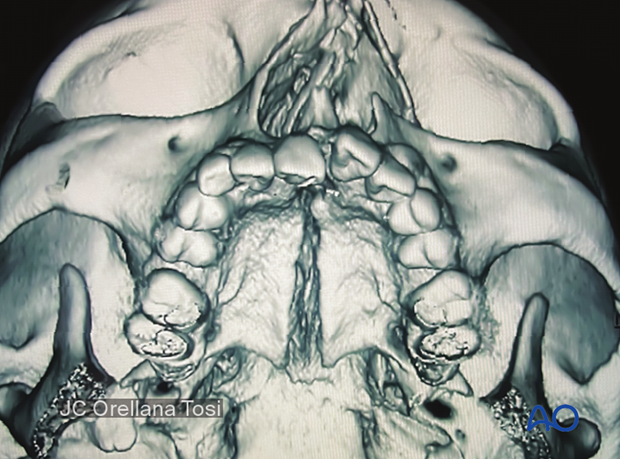

The 3D reconstruction shows the palatal fracture pattern and displacement separated parallel to the midline suture.